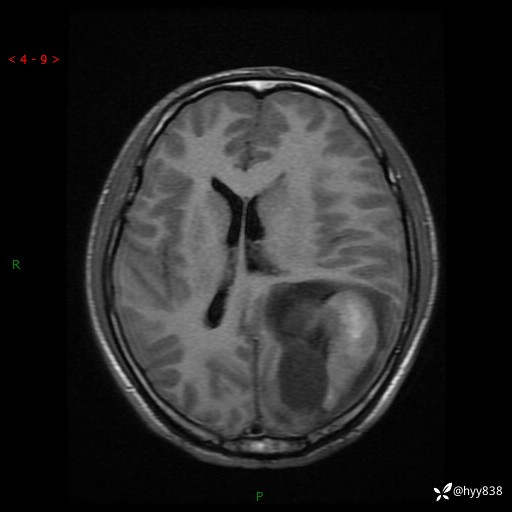

病例年轻小伙,头痛伴呕吐半年,渐进性加重1月。疑难病例,第一次见--结果公布~

性别:男

年龄:21岁

简要病史:头痛伴呕吐半年,渐进性加重1月

颅脑MRI平扫+增强